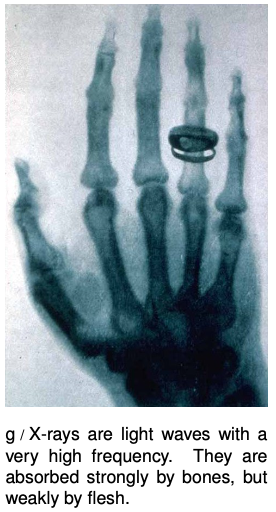

Light is an interesting case, since although it can travel through matter, it is not itself a vibration of any material substance. Thus we can look at the star Sirius, km away from us, and be assured that none of its light was absorbed in the vacuum of outer space during its 9-year journey to us. The Hubble Space Telescope routinely observes light that has been on its way to us since the early history of the universe, billions of years ago. Of course the energy of light can be dissipated if it does pass through matter (and the light from distant galaxies is often absorbed if there happen to be clouds of gas or dust in between).